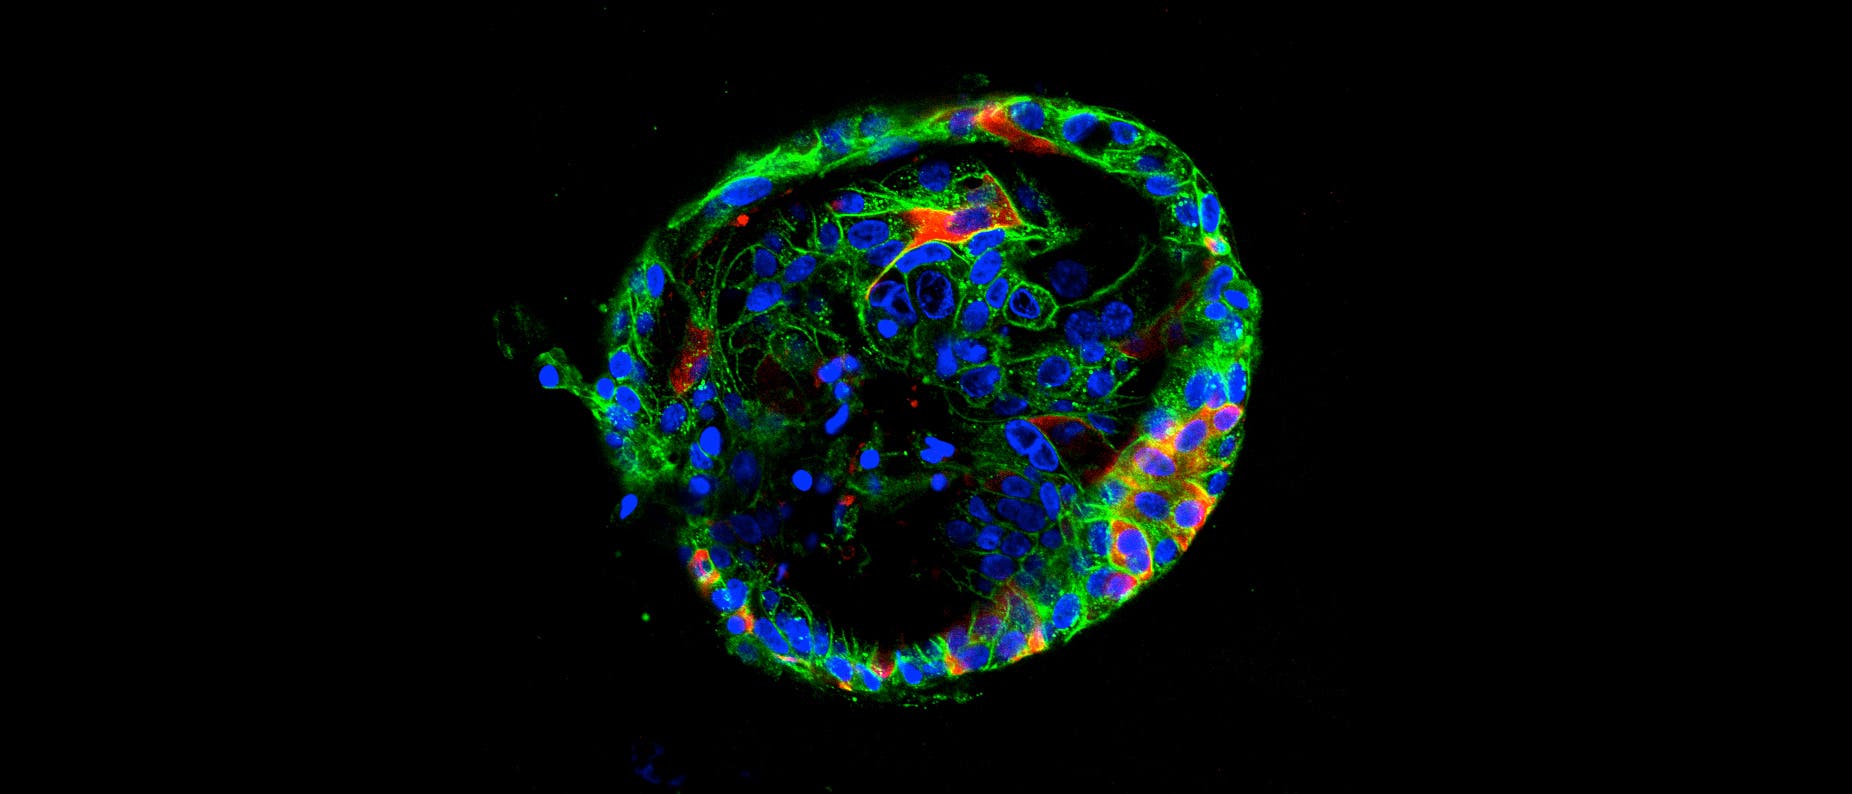

Aus Autopsien und Erfahrungen mit Erkrankten in den Kliniken wissen Ärzte, dass Sars-CoV-2 verheerende Auswirkungen auf verschiedene Organe haben kann. Um zu untersuchen, was das neuartige Coronavirus im Körper anrichtet, züchten Forscherinnen und Forscher nun Miniaturorgane im Labor. Bisher nämlich war unklar, ob das Virus die Schäden direkt verursacht oder ob die mit der Infektion einhergehenden Komplikationen verantwortlich sind. Nun aber enthüllen Studien an diesen Organoiden die Vielseitigkeit des Virus.

Mehrere Arbeitsgruppen stellen Organoide her, um herauszufinden, wohin das Virus im Körper wandert, welche Zellen es infiziert und was für Schäden es anrichtet. Die Untersuchungen zeigen nicht nur, dass es sich Zutritt zu Lunge, Leber, Nieren und Darm verschafft. Forscher versuchen auch, mit den Miniorganen Medikamente für die Therapie von Covid-19 zu finden, indem sie das Gewebe mit verschiedenen Wirkstoffen behandeln.

»Das Schöne an Organoiden ist, dass sie der wahren Morphologie von Geweben ähneln«, sagt Thomas Efferth, Zellbiologe an der Johannes Gutenberg-Universität in Mainz. Üblicherweise untersuchen Virologen das Verhalten von Viren mit Hilfe von Zelllinien oder aus Tieren gewonnenen Zellen. Diese sind Forschern zufolge aber kein sehr gutes Modell für die Sars-CoV-2-Infektion, weil sie nicht genau nachbilden, was mit diesen Geweben im Inneren des Körpers passiert.

Organoide könnten besser nachstellen, was Sars-CoV-2 mit menschlichem Gewebe macht, sagt Núria Montserrat, Stammzellforscherin am Institute for Bioengineering of Catalonia in Barcelona. Montserrat zufolge können die Miniorgane so gezüchtet werden, dass sie mehrere Zelltypen enthalten und innerhalb von Wochen die Form des gewünschten Organs annehmen. Zudem seien sie kostengünstiger als Tiermodelle und umgehen die ethischen Fragen, die diese aufwerfen.